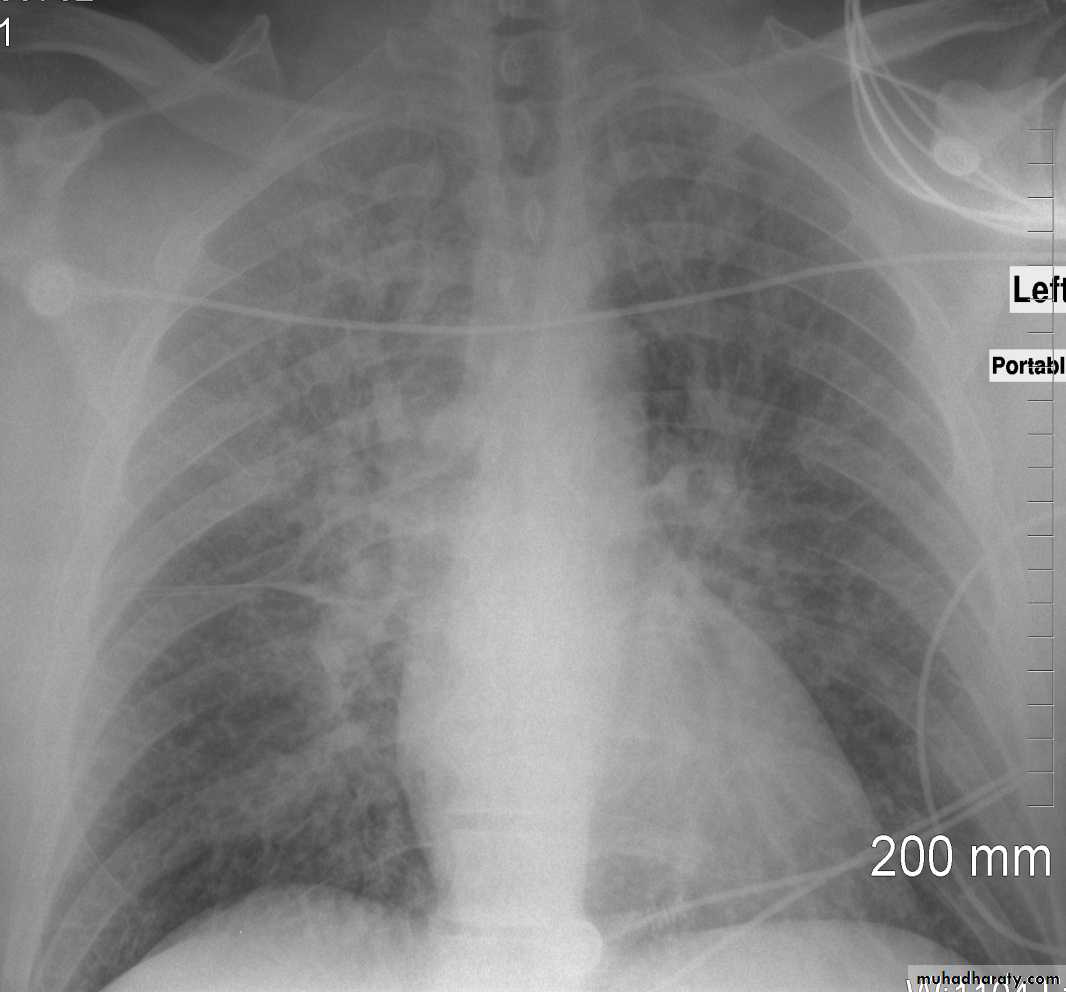

Congestive cardiac failure (CCF) is a form of cardiac failure which is primarily manifested by the heart inability to pump the volume of blood. It can affect the left (common) or right cardiac chambers or both.

Radiographic features

Chest radiograph

With left sided congestive cardiac failure, the features are that of pulmonary edema which includes:

central pulmonary venous congestion ( prominent hilum )

cephalisation of pulmonary veins ( upper lobe pulmonary venous diversion )

pulmonary interstitial oedema

pulmonary alveolar oedema

Cardiomegaly

Pleural effusion

Interstitial pulmonary edema

radiograph include if pressure > 25 mmHg the findings of :

cardiac size/cardio-thoracic ratio: useful for assessing for an underlying cardiogenic cause or associationbat wing pulmonary opacities

presence of peri-bronchial cuffing

septal lines: Kerley lines become more prominent

pleural effusions

pulmonary venous engorgement/pulmonary blood flow distributionupper lobe pulmonary venous diversion

Alveolar pulmonary edema